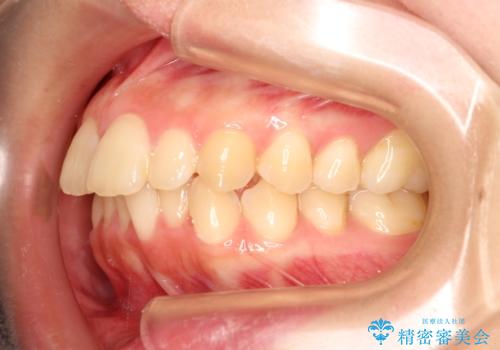

かぶせ物の計画を立てる際に、歯の傾きや位置を正しい位置に移動させてから、かぶせ物を装着したほうが審美性、機能性、清掃性において優れた治療が可能となることがあります。